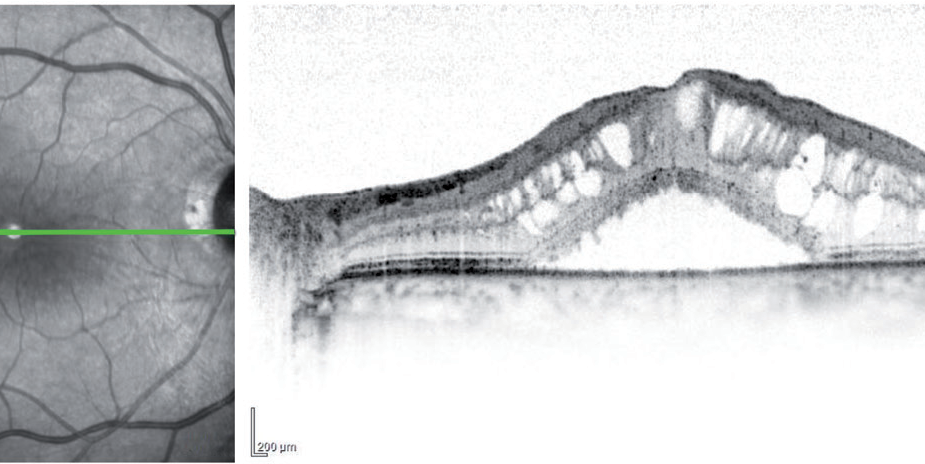

Tomografía de coherencia óptica (OCT, por sus siglas en inglés). La OCT es otra manera de observar en detalle la retina. Un equipo especializado analiza la estructura de la retina por medio de captura de imagenes en forma muy similar a tomar una fotografía y provee imágenes muy detalladas de su espesor. Esto ayuda al médico a detectar alguna fuga y medir la inflamación o edema de la mácula.